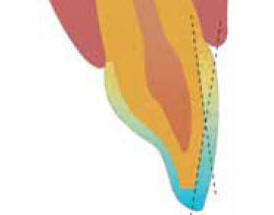

| El rebaje

del esmalte vestibular se hizo en la forma del esquema, es

importante dejar esmalte para su posterior grabado con acido

ortofosfórico al 37% |

Esquema para el tallado de carillas

convencionales |